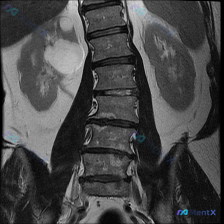

只看这张腰椎MRI冠状位,除了明显的侧弯,还有两个容易漏的关键发现

整理到一张腰椎MRI T2加权序列冠状位的影像资料,先不看后续的其他序列和临床信息,只看这张图的话,有几个点比较值得拿出来讨论: 1. 脊柱力线确实有明显异常,侧弯方向和顶端位置也比较清楚 2. 椎间盘的信号和椎间隙高度有非对称性改变 3. 扫描野里除了腰椎,还能看到双侧肾脏,肾盂肾盏区似乎有信号变...

整理了一张腰椎MRI T2序列冠状位图像的资料,大家可以先看看核心影像表现: - 腰椎整体向右侧凸(凸向右侧,凹向左侧) - 各椎体高度大致正常,边缘可见骨赘形成 - 腰椎下段(L4-L5、L5-S1)椎间隙不对称,凹侧更紧凑 - 冠状位上左侧下方椎间孔区域脂肪信号略显模糊,空间受限 没有提供患者的...

整理到一份腰椎MRI-T2冠状位的影像资料,第一眼就能看到明确的脊柱侧弯——腰椎呈C型向左侧凸。 但仔细看还有几个点: 1. 侧弯凸侧(右侧)椎体边缘有不同程度骨赘形成 2. 双侧小关节增生明显,关节周围有高信号 3. 椎间隙左右不对称,凹侧(左侧)椎间孔空间看起来受压缩 4. 目前层面没看到明确的...

整理到一份腰椎MRI T2冠状位的影像资料,大家先看一眼: 核心影像表现: - 腰椎明显向左侧弯曲,呈“C”型,顶点在腰椎中部 - 椎体形态基本完整,未见明确骨质破坏或压缩 - 椎间盘T2信号普遍减低(偏暗),提示脱水退变 - 侧弯节段椎间隙左右不对称:右侧张开,左侧闭合 - 两侧旁椎肌肉(腰大肌、...

整理到一份腰椎MRI T2序列冠状位的影像分析,第一眼确实很容易被「脊柱侧弯」抓住注意力——影像上腰椎序列明显向左侧弯,多节段椎间盘T2信号减低,椎间隙左右不对称,典型的退行性改变表现。 但再看下去,右肾区有一个圆形的T2高信号灶,报告里单独提了这个「除脊柱以外最显著的异常发现」。 如果只看到前期的...

整理到一份影像读片资料,有点意思,放出来讨论下。 先看核心发现: - 腰椎MRI T2冠状位:明显向左侧凸畸形;椎体边缘骨赘形成,部分椎间隙非对称性变窄;凹侧椎间孔区域相对狭窄。 - 额外发现:右侧(图像左侧)肾脏内见边界尚清的明显高信号影。 影像科初步分析里提了“退行性脊柱侧弯”的依据很足,但同时...